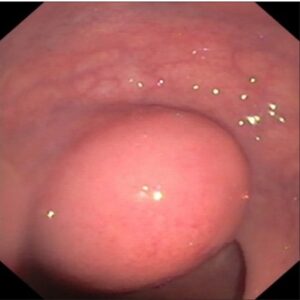

The authors present the case of a 63-year-old woman with a past medical history of arterial hypertension, dyslipidemia and type 2 diabetes mellitus, who presented to the gastroenterology office for a screening colonoscopy due to a family history of colon cancer. The colonoscopy showed a subepithelial lesion of about 30 mm in diameter, with normal overlying mucosa, in the left lateral wall of the rectum, approximately at 9 cm from the superior anal margin (figure 1). No other lesions were found in the other colon segments.

Figure 1: Subepithelial lesion, located at the left lateral wall of the rectum.